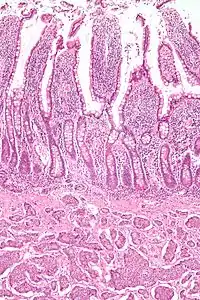

Small intestinal neuroendocrine tumor at bottom third of image, showing the typical intramural (within the wall) location, and overlying intact epithelium. H&E stain.

NETs are often small, yellow or tan masses, often located in the submucosa or more deeply intramurally, and they can be very firm due to an accompanying intense desmoplastic reaction. The overlying mucosa may be either intact or ulcerated. Some GEP-NETs invade deeply to involve the mesentery.[72] Histologically, NETs are an example of "small blue cell tumors," showing uniform cells which have a round to oval stippled nucleus and scant, pink granular cytoplasm. The cells may align variously in islands, glands or sheets. High power examination shows bland cytopathology. Electron microscopy can identify secretory granules. There is usually minimal pleomorphism but less commonly there can be anaplasia, mitotic activity, and necrosis.